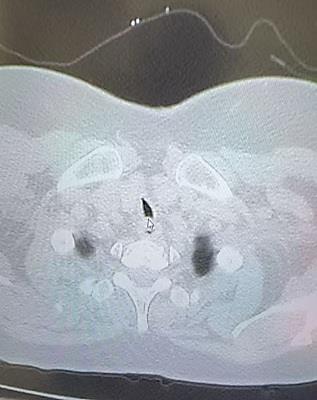

患者系胆囊结石伴胆囊炎入院,既往有车祸伤行开颅手术及气管切开术。体格检查可见颈部有一明显疤痕,CT示:胸锁关节上缘水平气管管腔局限性狭窄。患者平时活动后有气短症状。